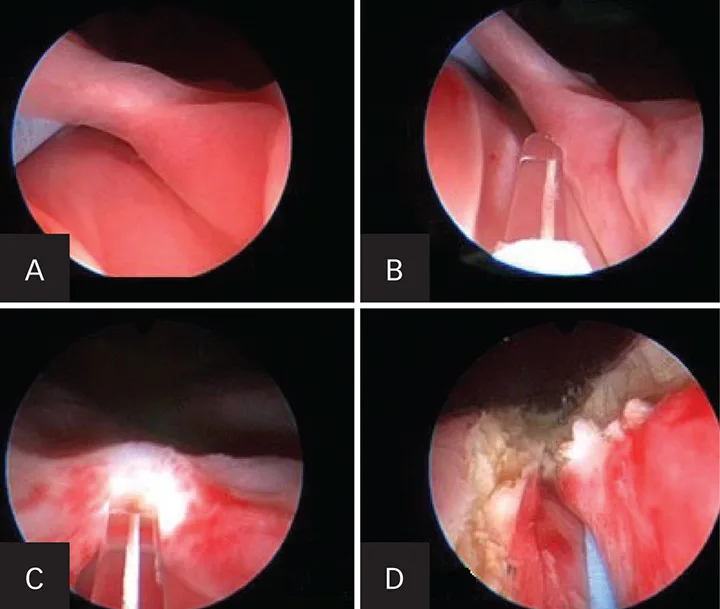

A more applicable procedure for essential renal hematuria is sclerotherapy for topical ureteral infusions (Figure 6). This has been performed in veterinary medicine and is most useful when the ureter is too small to allow ureteroscopic access.4

Figure 6. Retrograde ureteropyelogram during sclerotherapy in a female dog with idiopathic renal hematuria in dorsal recumbency during cystoscopy and fluoroscopy.

The procedure is performed with cystoscopic and fluoroscopic guidance in which a cauterizing sclerosing agent is carefully infused into the renal pelvis to stop the bleeding. The success rate is over 75%, and the procedure avoids the need for ureteronephrectomy. Between 25% and 33% of dogs will have bilateral benign renal bleeding with this condition, so nephrectomy should be avoided when possible.